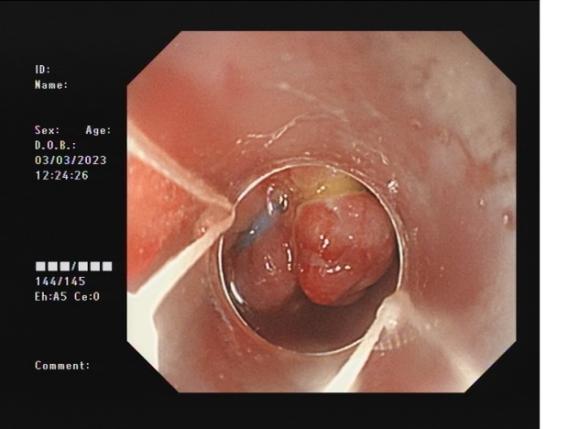

0d0b80a96701483cbcbf8b67351feac3.Jpeg8f7177645651428ca3a0f3c87dfd559d.Jpeg

直腸側向發育性腫瘤      內鏡下黏膜下剝離術后創面

內鏡下黏膜剝離術(ESD):治療巨大平坦息肉,早期癌及癌前病變,黏膜下腫瘤等。